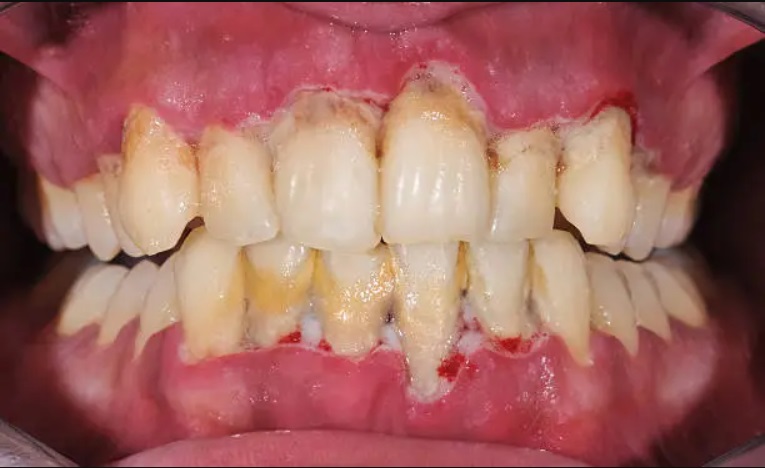

Gum disease, or periodontal disease, is a chronic bacterial infection that affects the gums and supporting structures of the teeth. It starts with the buildup of plaque, a sticky film of bacteria that forms on the teeth. When plaque is not removed through regular brushing and flossing, it hardens into tartar, which can only be removed by a dental professional. Tartar buildup irritates the gums, causing them to become red, swollen, and prone to bleeding. This early stage of gum disease is known as gingivitis.

If left untreated, gingivitis can progress to periodontitis, a more advanced form of gum disease. Periodontitis occurs when the infection spreads beneath the gum line, leading to the destruction of the supporting tissues and bone. As the disease progresses, pockets form between the gums and teeth, allowing more bacteria to accumulate. Without prompt treatment, this can result in tooth loss and other serious complications.

Periodontitis is an advanced form of gum disease that occurs when gingivitis is left untreated. It involves the inflammation and infection of the supporting structures of the teeth, including the gums, bone, and ligaments. As periodontitis progresses, the pockets between the gums and teeth deepen, allowing bacteria to thrive and cause further damage. Without intervention, periodontitis can lead to tooth loss and other complications. Treatment for periodontitis usually involves a combination of professional deep cleaning procedures, medication, and, in severe cases, surgery. Early detection and treatment are crucial to prevent irreversible damage and maintain a healthy smile.